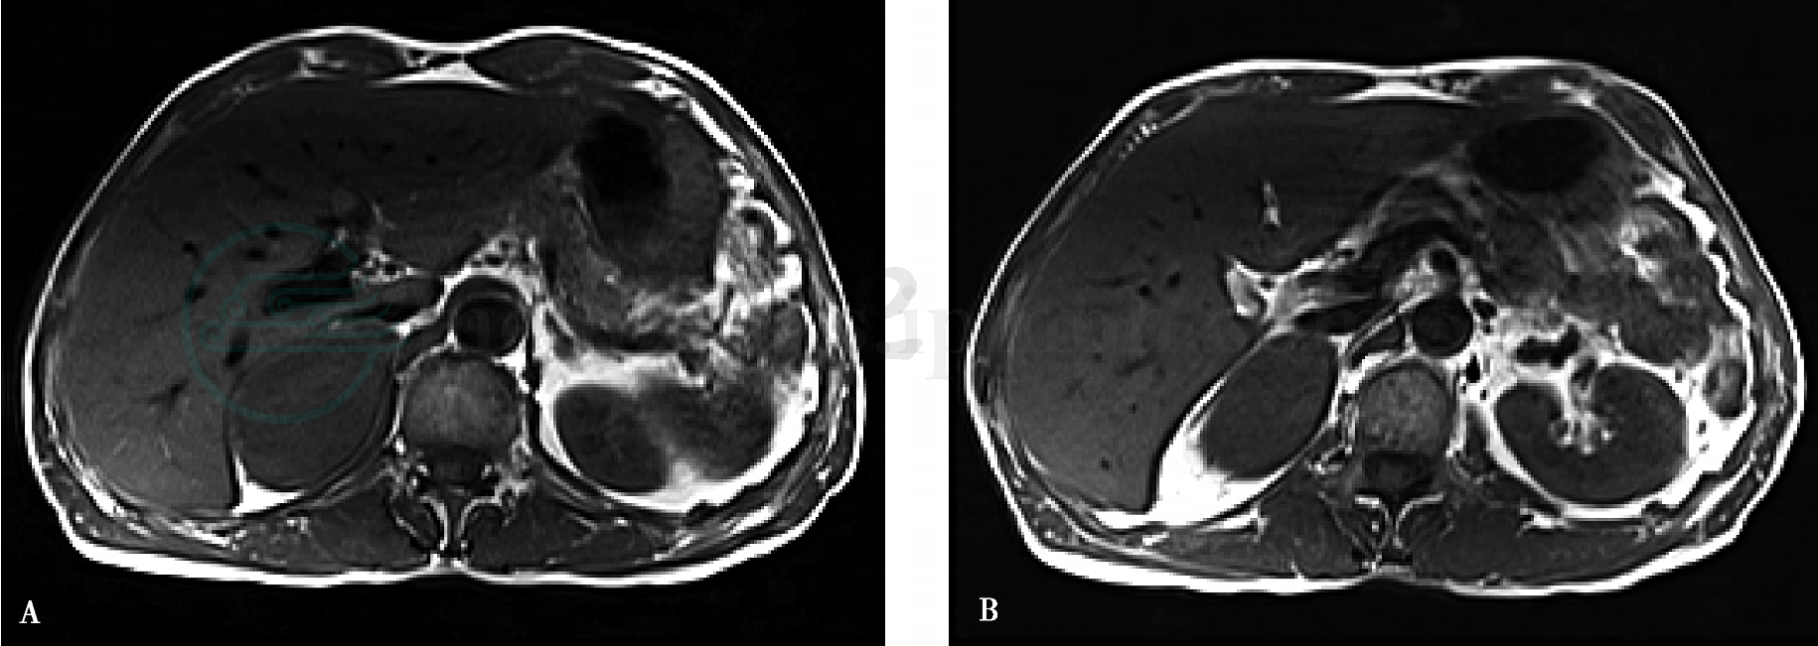

图5 神经节细胞瘤

注:A~G.右侧肾上腺区可见一椭圆形软组织团块,边缘光滑,界限清晰,邻近肾上腺受压向前下方移位,同侧肾脏受压向下移位;A、B. T1WI,病变以等信号為主,內有小片状稍低信号;C.T2WI,病变信号不均匀,以稍高信号為主,外周及內部可见条片状高信号和点条状低信号;D.脂肪抑制T1WI动脈早期,病变外周呈不规则的轻度強化,中心无強化;E、F、G.脂肪抑制T1WI动脈晩期、靜脈期及平衡期,病变持续性強化,強化范围由外周向中心逐渐扩大。